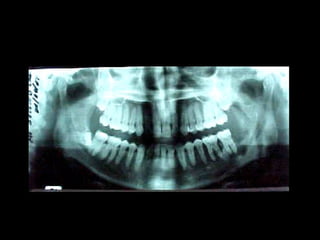

La periodontitis, denominada comúnmente piorrea, es una enfermedad que

inicialmente puede cursar con gingivitis, para luego proseguir con una pérdida de

inserción colágena, recesión gingival, e incluso la pérdida de hueso, en el caso de

no ser tratada, dejar sin soporte óseo al diente. La pérdida de dicho soporte

implica la pérdida irreparable del diente mismo.

De etiología bacteriana que afecta al periodonto (el tejido de sostén de los dientes,

constituido por la encía, el hueso alveolar, el cemento radicular y el ligamento

periodontal) se manifiesta más comúnmente en adultos mayores de 35 años, pero

puede iniciarse en edades más tempranas.

Periodontitis

Una periodontitis según su grado de afectación dental se clasifica en: leve,

moderada o grave. Y según su extensión se denomina: localizada o

generalizada.

Las periodontitis desde 1999 se han clasificado (ASP) en: crónicas,

agresivas y asociada a estados sistémicos.